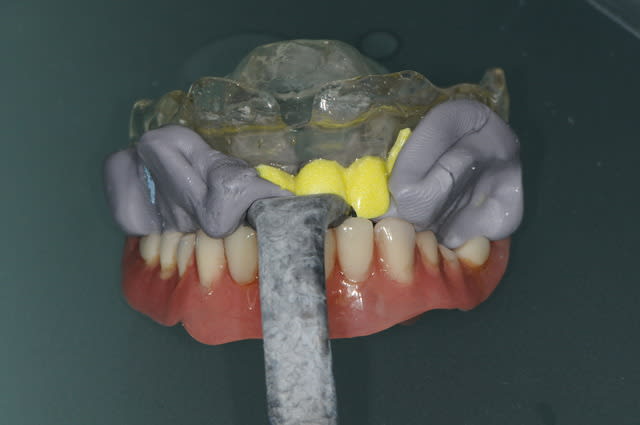

des photos ?

ok , en voilà...

ceux sont les photos du guide radio.

Mon prothésiste est un petit rigolo qui s'amuse à colorer les dents.

Ici le guide radio est préparé pour laisser passer l'embout de calage lors de la tomosynthèse de façon à ce que les deux appareils soient parfaitement stables.

les deux incisives centrales sont donc meulées.